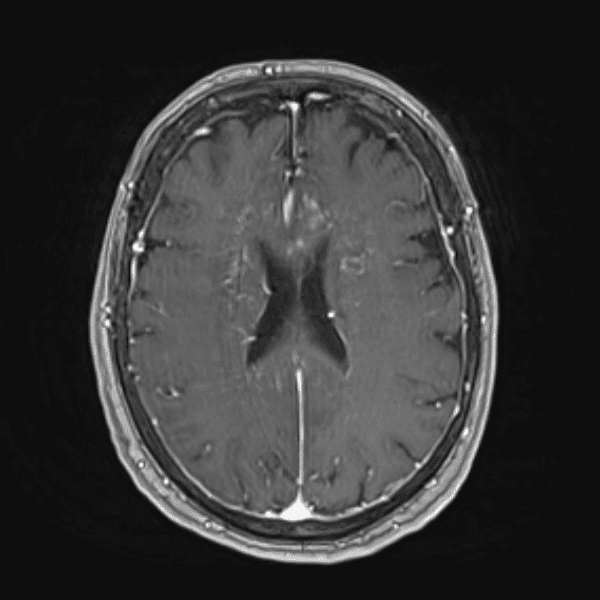

Classic Cases